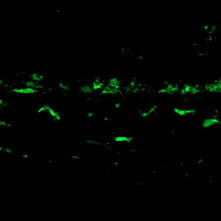

Comparison with our conventional product (rabbit polyclonal antibody)

Polyclonal Antibody

(Product No. 019-19741)

Monoclonal Antibody

(Product No. 018-28523)

Species: Rat

Site: Cerebral cortex

Sample: Frozen section

Antibody concentration: 1:200

Data by courtesy of

Dr. Nakajima, Faculty of Science and Engineering, Soka University